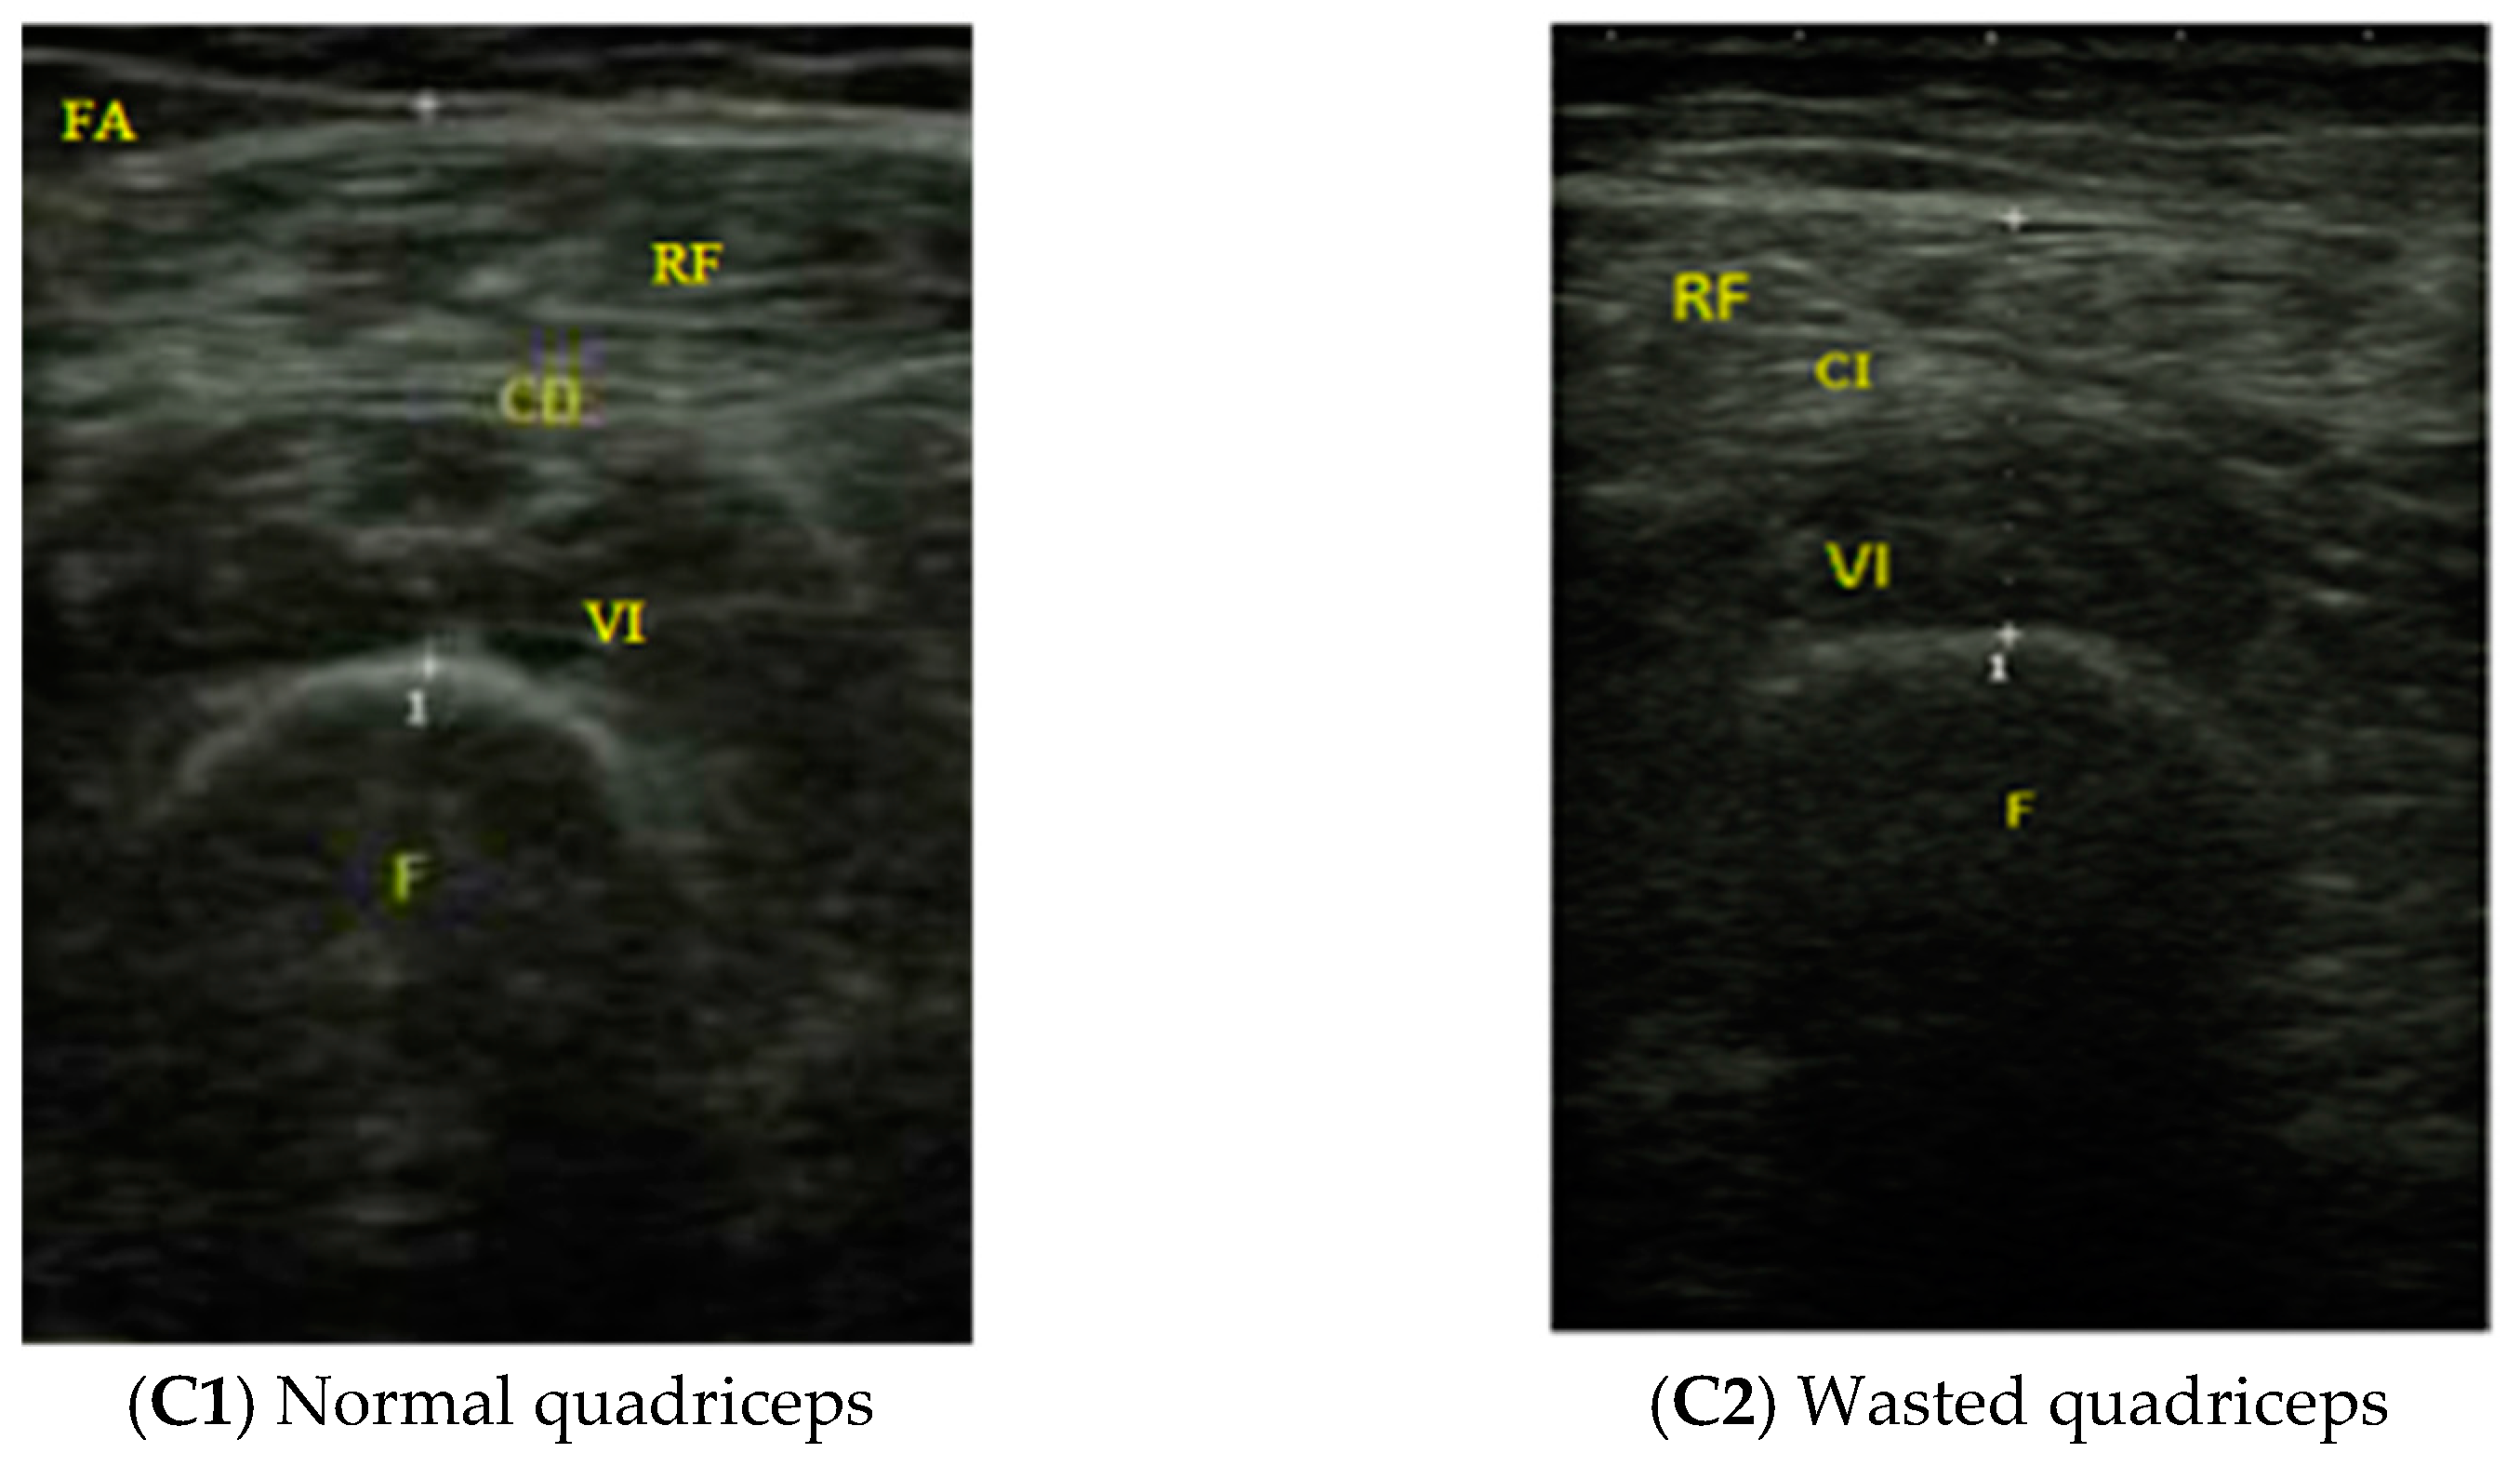

2.2.4. Muscle Ultrasound Exploration